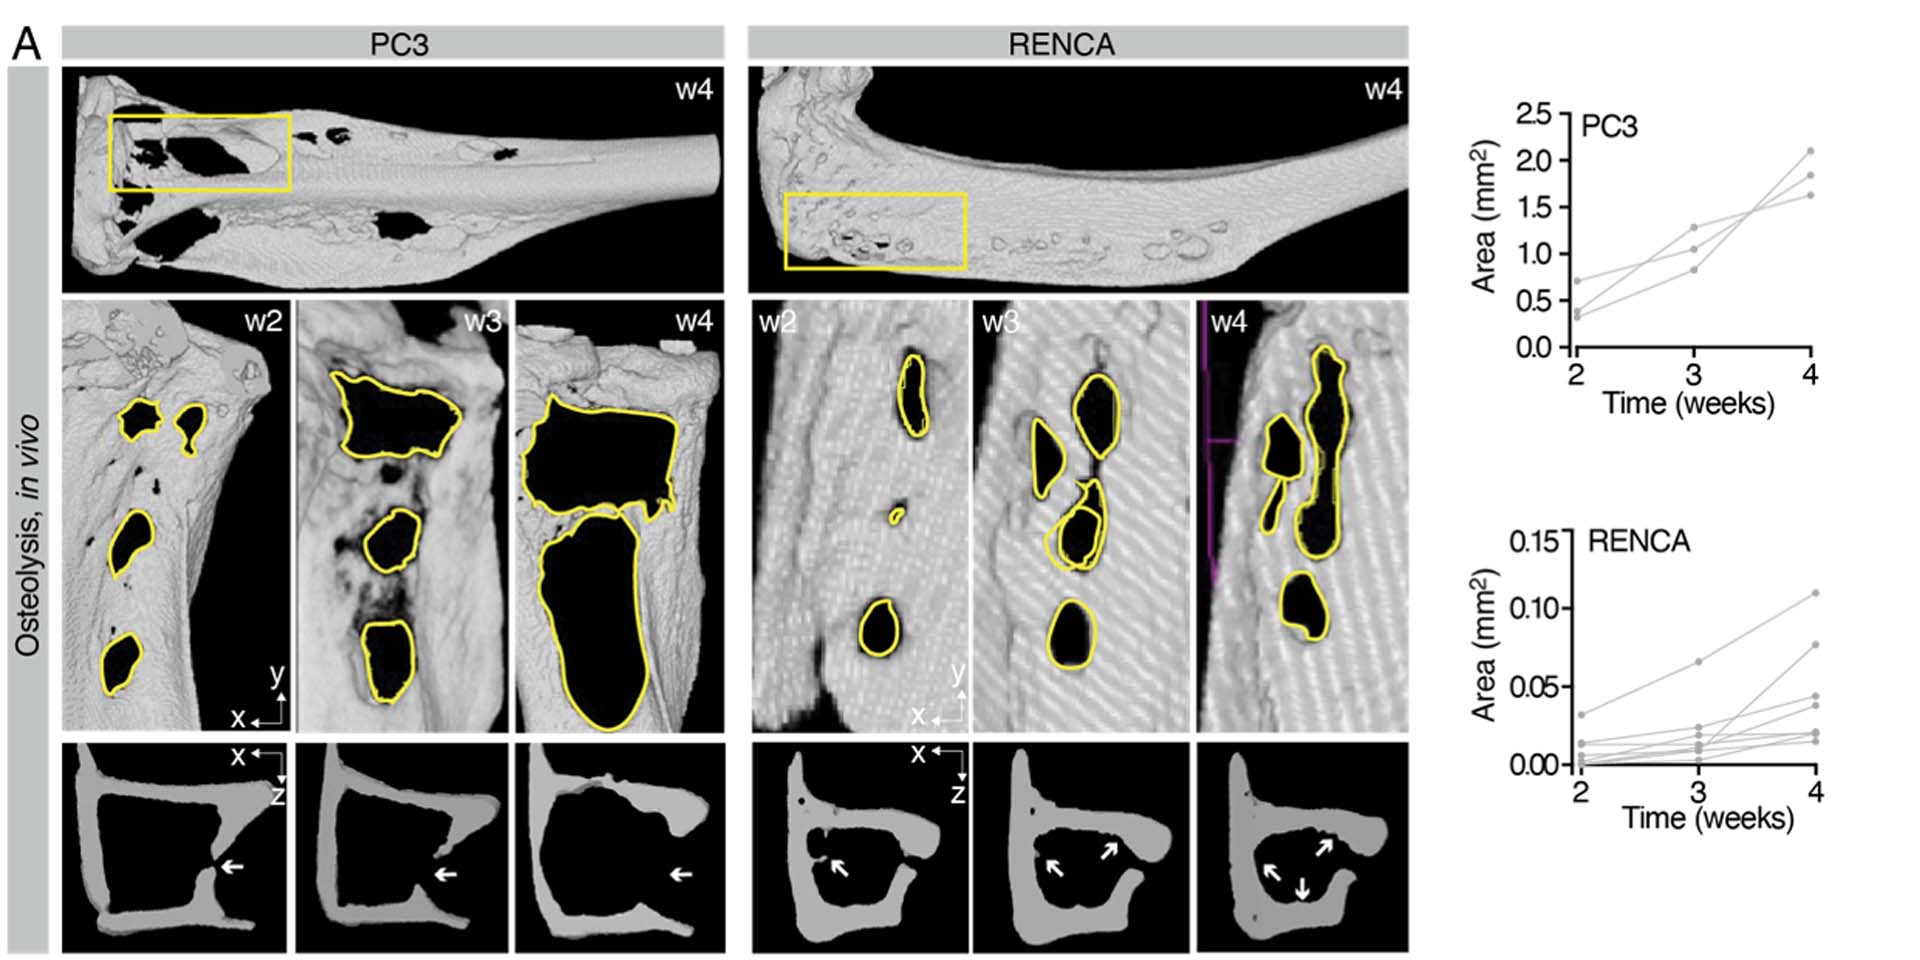

Simulazione della progressione osteolitica all’interno di A(BM)². A. Osteolisi indotta dal tumore, in vivo, analizzata tramite µCT; sono riportate immagini della progressione nel tempo e la quantificazione dell’area ossea riassorbita (lesioni singole, n = 3–7 lesioni/osso).

A. Tumor-induced osteolysis, in vivo, by µCT analysis; pictures of progression over time and quantification of bone area resorbed (single lesions, n=3-7 lesions/bone) are shown.

The images above showcase how the progression of osteolysis is reproduced both in in-vivo experiments and in the A(BM)² simulation. In mice, implantation of tumor cells (PC3 or RENCA) leads to progressive bone loss, measured by µCT, with PC3 cells being more osteolytic than RENCA cells.

Immunofluorescence analysis confirms that this process is associated with increased recruitment of osteoclasts (OC) by PC3. The same behavior is then recreated in the computational model, where osteoclasts are activated when tumors are located near the bone surface, leading to tissue resorption and replacement with tumor cells.

In summary, the figure demonstrates that A(BM)² is capable of consistently reproducing the tumor-specific differences observed in vivo in the process of osteolysis, highlighting the importance of tumor type and its proximity to bone in determining the severity of bone destruction.